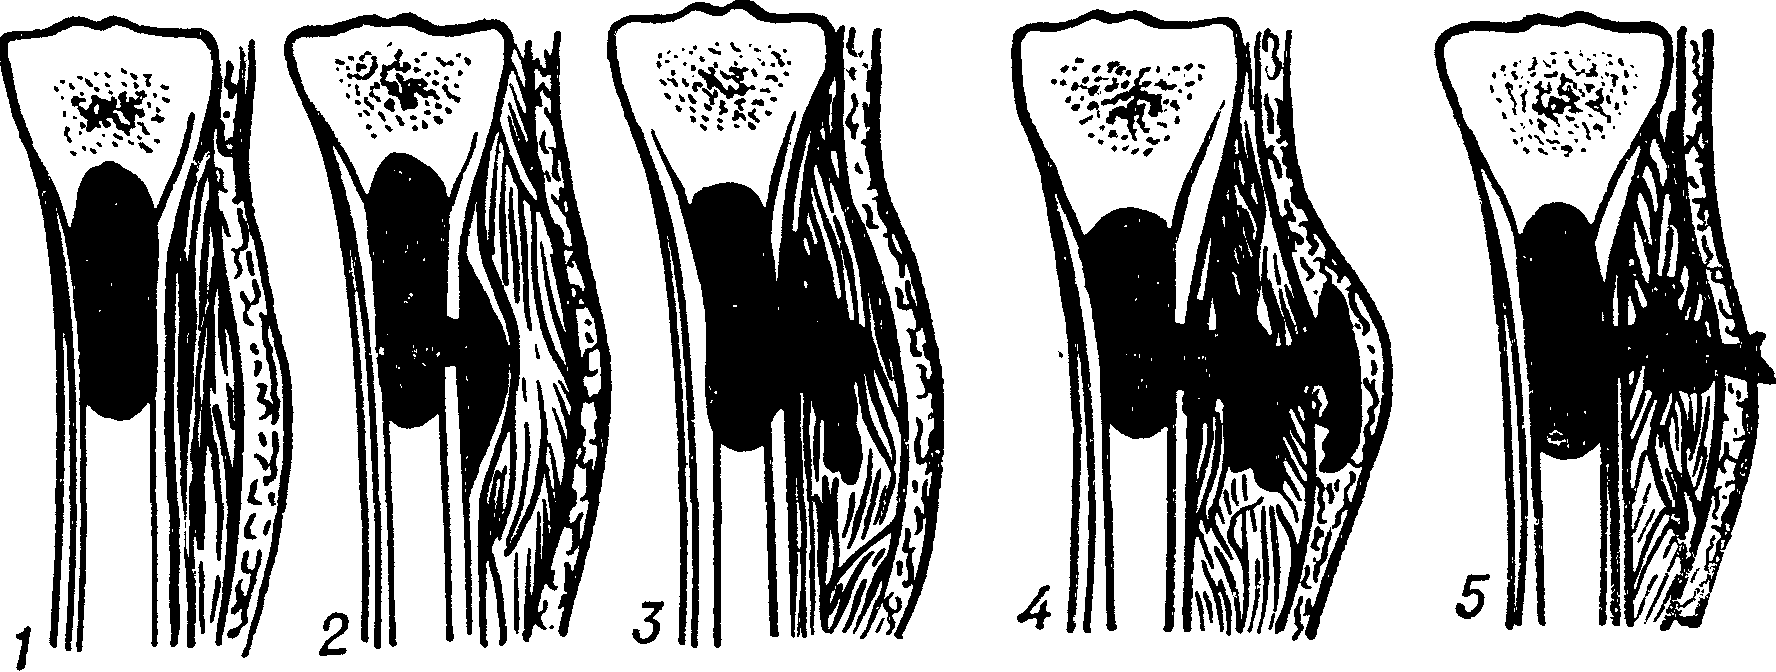

Дальнейшее течение заболевания типично: патогенная микрофлора начинает активно размножаться в костномозговом канале с формированием воспаления и гноеобразованием. При этом повышается внутрикостное давление. Дальнейшее распространение гноя может производиться несколькими путями:

- В направлении эпифиза (окончания кости) с последующим прорывом в полость сустава и возникновением гнойного артрита.

- В надкостницу. Это сопровождается ее отслойкой и частым формированием свищей (выход гнойных масс на поверхность кожи через все мягкие ткани, которые окружают воспалительный костный очаг).

- На все структуры кости. Формируется околокостная флегмона с последующим расплавлением окружающих тканей, появлением спаек, контрактур, отека костного мозга.

- Генерализация с поражением других костей, внутренних органов и развитием сепсиса.

Считается, что прорыв гноя в сторону эпифиза или надкостницы является наиболее относительно благоприятным направлением. Генерализация инфекции часто сопровождается развитием системных септических осложнений с нередким летальным исходом.